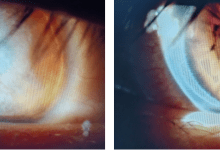

病例摘要 患者女性,23岁。因左眼视力下降、涩磨就诊。患者于2017年11月6日拟行近视眼矫正手术于解放军第一五九医院眼科就诊,术前视力右眼为0.01,左眼为0.01。双眼睑结膜轻度充血,可见散在滤泡和结石,球结膜无充血,角膜透明。2017...